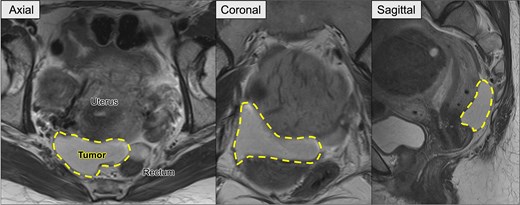

Preoperative pelvic MRI showing the recurrent retroperitoneal tumor (dashed line). Axial view: The tumor is located posterior to the uterus and anterior to the rectum. Coronal view: The tumor extends horizontally across the pelvic cavity. Sagittal view: The tumor is situated between the bladder and rectum, occupying the posterior pelvic space.